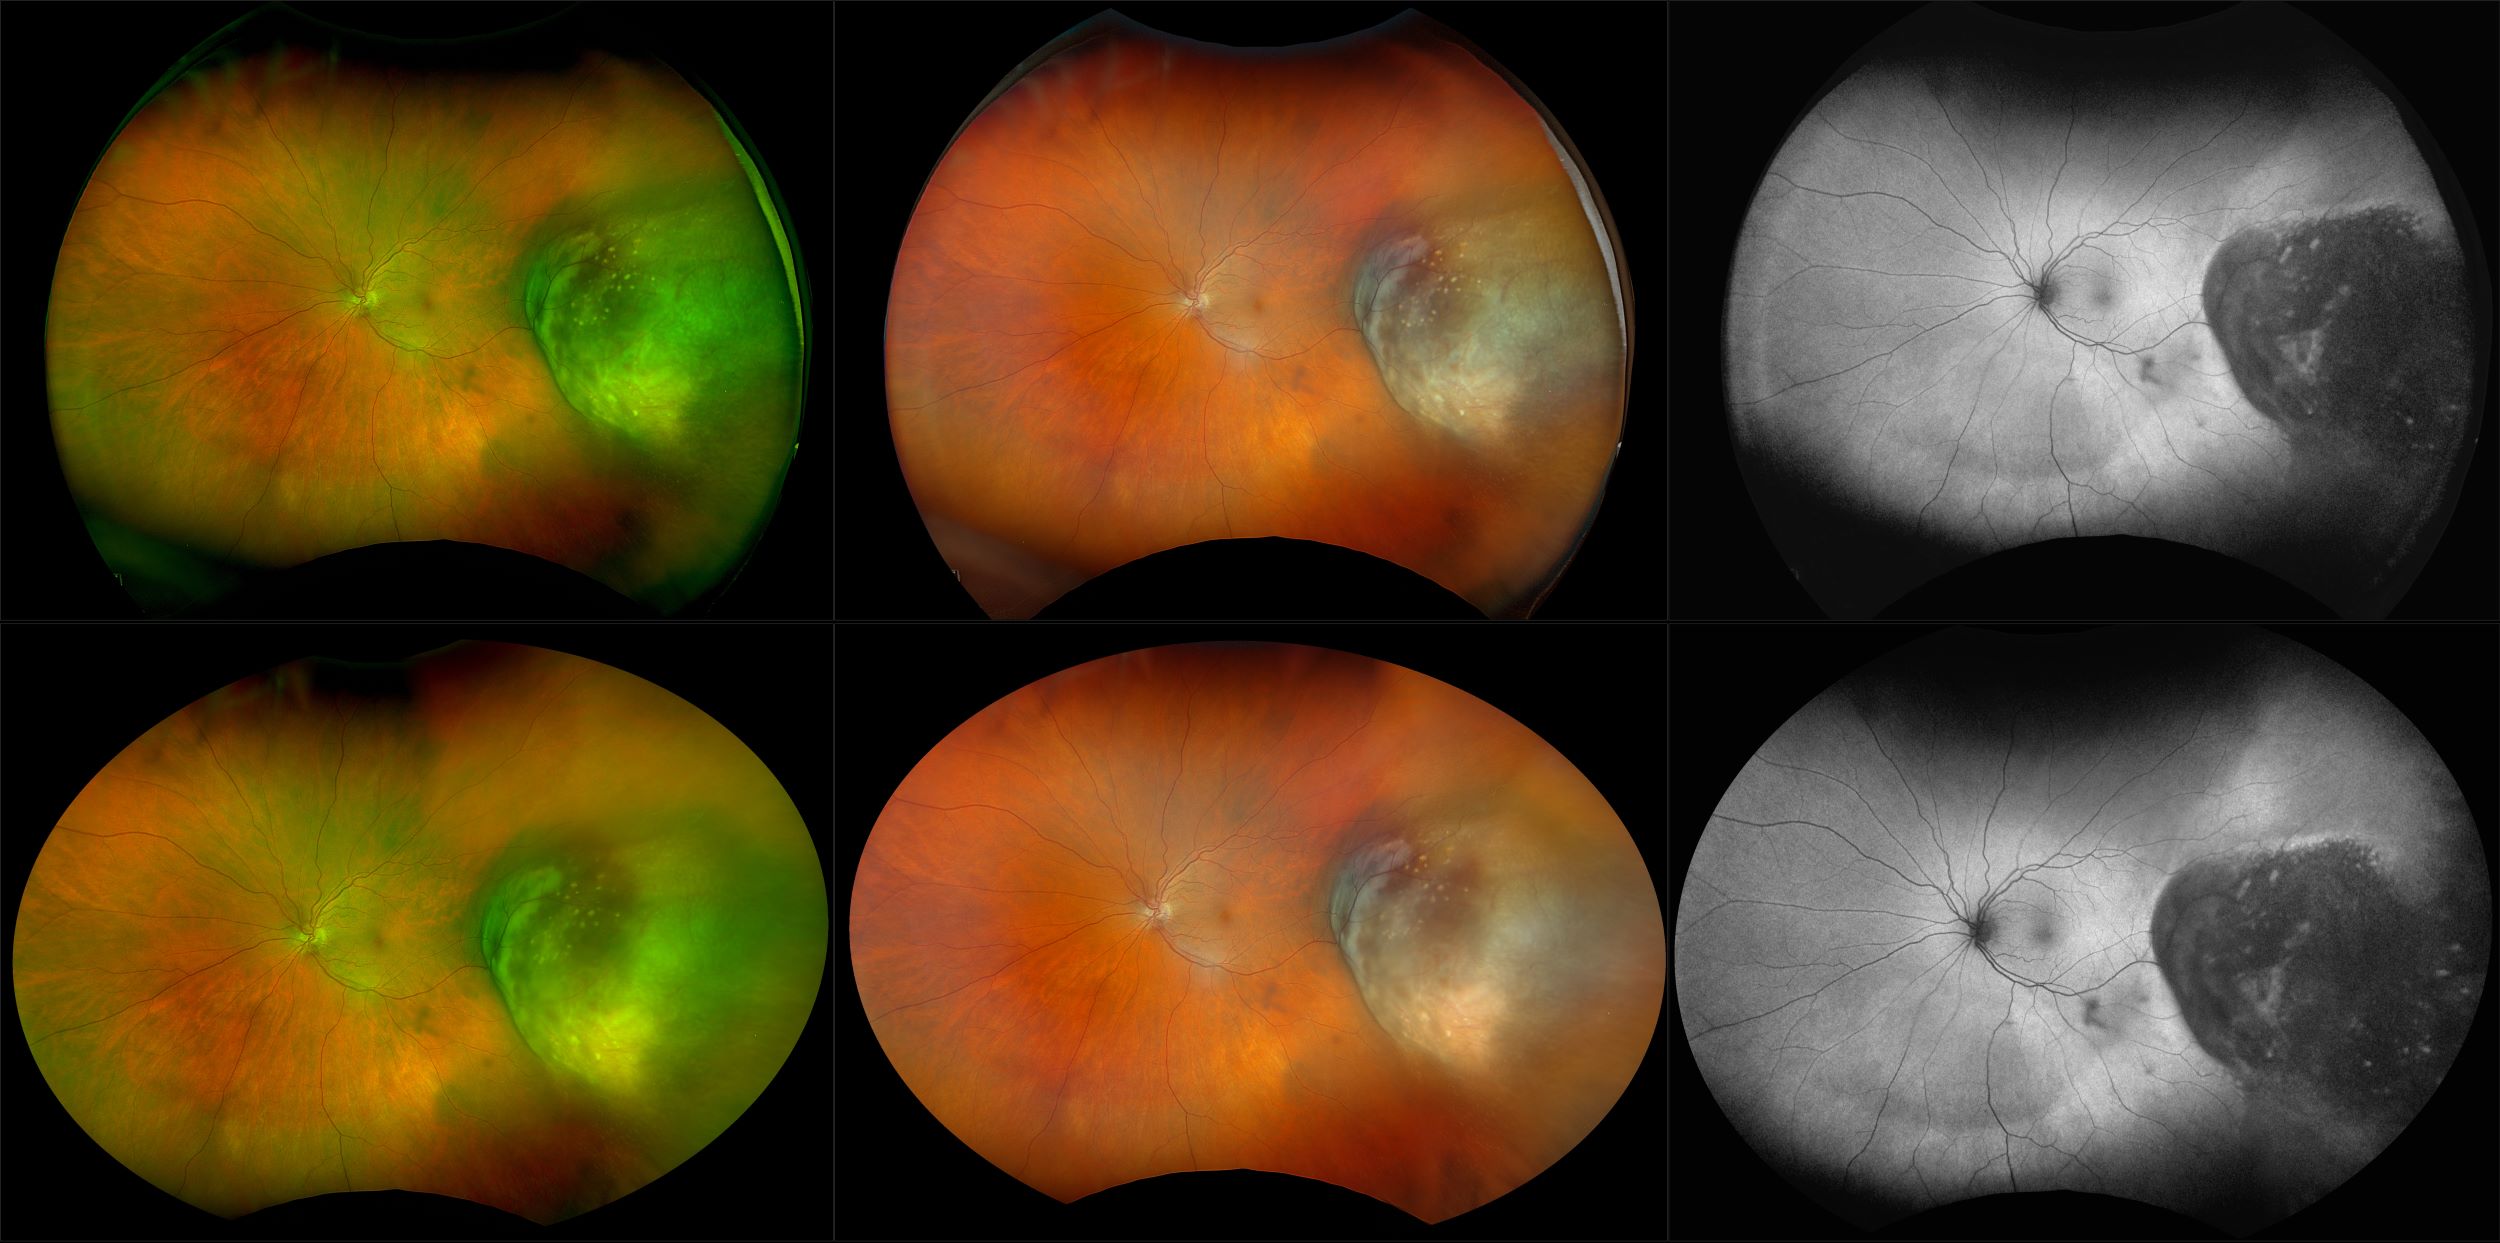

California - Choroidal Nevus, RG, AF

A choroidal nevus is simply an accumulation of melanocytes in the choroid. They are a space occupying mass or a benign melanoma. Choroidal nevi are slate gray in color, have indistinct margins, and may be slightly elevated (1-2 diopters). Since they are in the choroid, they are usually only seen in the red separation and not the green. The green separation may show the RPE degeneration associated with nevi which is seen as pigment mottling and drusen.